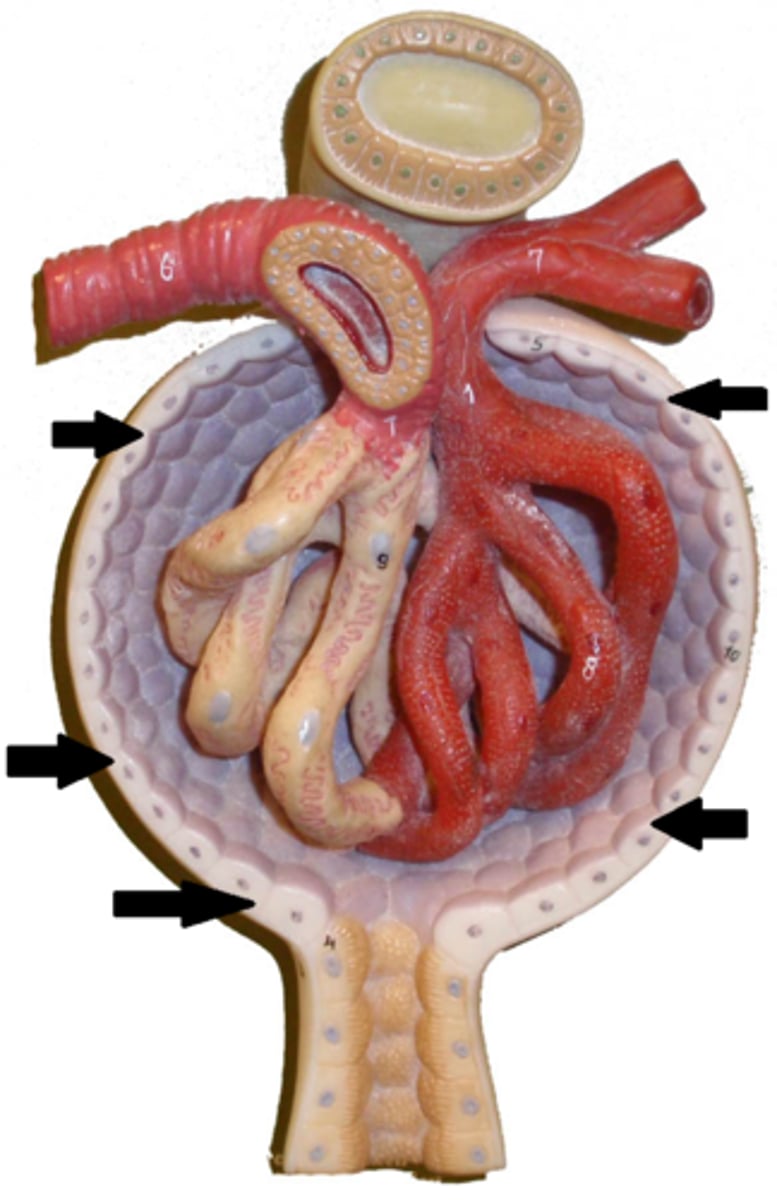

kidney

fibrous capsule

outer covering

renal cortex

renal medulla

renal papilla

major calyx

minor calyx

renal pelvis

renal pyramids

ureter

renal columns

renal artery

renal vein